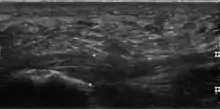

Medical imaging is not routinely needed. It is expensive and does not typically change how plantar fasciitis is managed.[15] When the diagnosis is not clinically apparent, lateral view X-rays of the ankle are the recommended imaging modality to assess for other causes of heel pain, such as stress fractures or bone spur development.[7]

The plantar fascia has three fascicles-the central fascicle being the thickest at 4 mm, the lateral fascicle at 2 mm, and the medial less than a millimeter thick.[19] In theory, plantar fasciitis becomes more likely as the plantar fascia's thickness at the calcaneal insertion increases. A thickness of more than 4.5 mm ultrasound and 4 mm on MRI are useful for diagnosis.[20] Other imaging findings, such as thickening of the plantar aponeurosis, are nonspecific and have limited usefulness in diagnosing plantar fasciitis.[13]

Three-phase bone scan is a sensitive modality to detect active plantar fasciitis. Furthermore, a 3-phase bone scan can be used to monitor response to therapy, as demonstrated by decreased uptake after corticosteroid injections.[21]